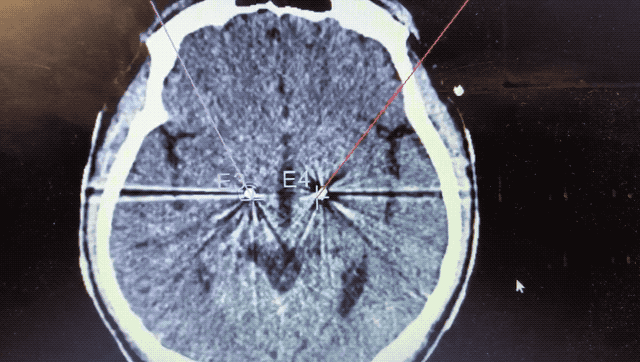

順利檢測到典型的核團(tuán)信號(hào)后,再次植入刺激電極到相應(yīng)位置,測試后即可完成單側(cè)的電極植入。對(duì)側(cè)只需借助機(jī)器人再次定位,并將檢測電極、刺激電極依次植入,最后,還需將刺激器植入患者胸前皮下。根據(jù)術(shù)后CT顯示,本手術(shù)雙側(cè)植入電極的位置與術(shù)前規(guī)劃路徑完全吻合,患者開機(jī)后,起搏器會(huì)開始沿刺激電極向患者核團(tuán)實(shí)施高頻電刺激,以減輕疾病癥狀,提高患者的生活質(zhì)量。

術(shù)后CT顯示雙側(cè)電極植入位置與規(guī)劃完全吻合